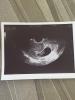

Увиделась сегодня со своим крохой. Уже такой большой ручки, ножки появились 🥰 в ПЦ как всегда фоточку не сделали, пойду через неделю платно.

Ктр 27

Жм 2,9

Чсс 161

Тут 8-9 недель, точный срок не помню. Ближе к 9